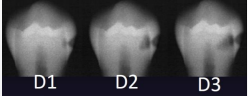

according to the ADA caries classification system, what is D1

to outer 1/3 dentin

according to the ADA caries classification system, what is D2

to middle 1/3 of dentin

according to the ADA caries classification system, what is D3

inner 1/3 of dentin

classify this according to radiographic presentation of the ADA

D1

classify this according to radiographic presentation of the ADA

D2

classify this according to radiographic presentation of the ADA

D3